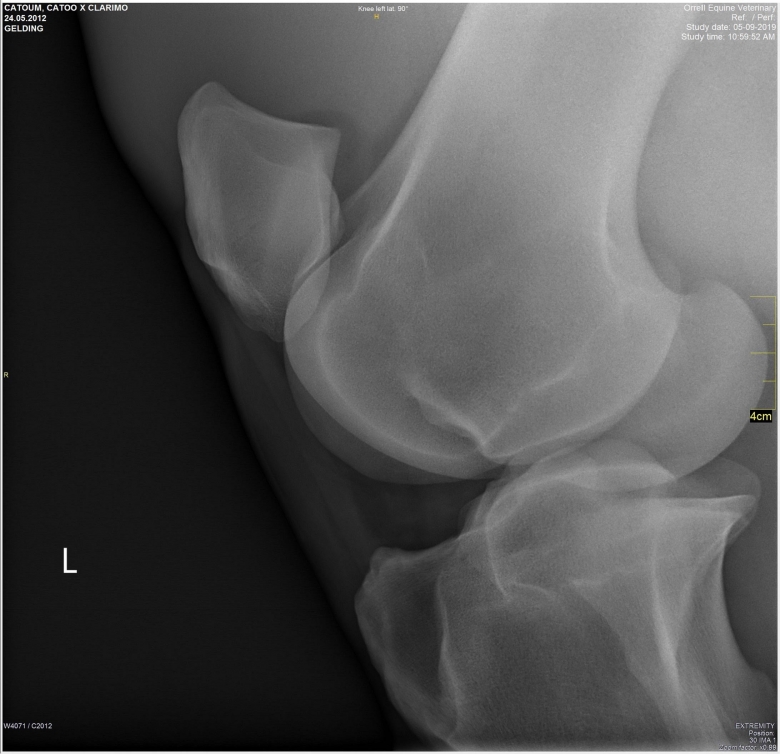

Snart dök det även upp röntgenplåtar, utan att Marina ens hade frågat efter dem. Röntgenbilderna skickade Marina vidare till två olika veterinärer för bedömning. Bägge såg lösa benbitar i ena hasen och Cecilia Grahn på Kungsbacka Hästklinik hade en mejlkonversation med den engelske veterinären ”Steve Orrell” som hade tagit bilderna. Att bilderna var falska och att det inte var den riktige Steve Orrell var det ingen som visste då. Han skrev att han hade sett hästen sedan den var tre år och argumenterade först emot de tre lösa benbitar som Cecilia Grahn hade hittat.

Lucas Bailey skickar bilder på röntgenplåtar. Marina Johansson låter två olika veterinärer bedöma bilderna. Bägge såg lösa benbitar i ena hasen och Cecilia Grahn på Kungsbacka Hästklinik hade en mejlkonversation med den engelske veterinären ”Steve Orrell” som hade tagit bilderna. ”Veterinären” skriver att han har sett hästen sedan den var tre år och argumenterar för att benbitarna saknar betydelse.